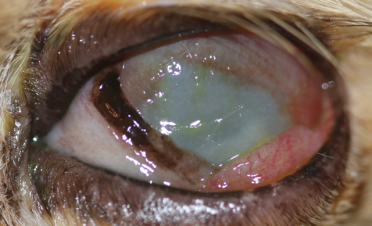

A los 15 días de tratamientos orales y tópicos la úlcera había disminuído hasta abarcar un 25% de la superficie corneal, y Bagheera ya no tenía apenas dolor.